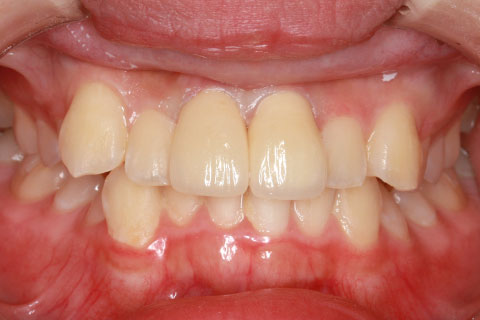

• オールセラミックの症例2

治療前

治療後

年齢・性別

45歳男性

治療期間

2ヶ月

抜歯

なし

治療費

70.4万円

備考

前歯8本の歯列不正によるセラミック治療

治療内容

歯質を削除し、セラミック冠をセメント合着

施術の副作用(リスク)

知覚過敏、歯髄炎、荷重負担